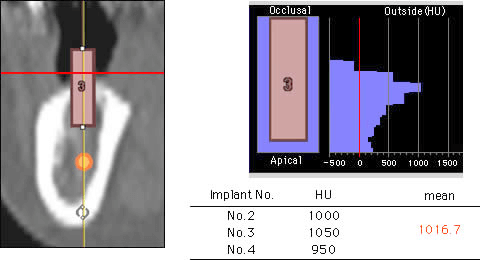

インプラント治療を希望し来院され、全顎的に高度の骨吸収を認めました(図1)。術前のCTデータをSimplantsにより3D構築し診断・計測したところ、下顎左側臼歯部の歯槽骨頂-下歯槽菅距離は第一第二大臼歯部で約9mmと近接、(図2)また、同部のハンスフィールド値からは歯槽頂部における皮質化の昂進を認めました(図3)。インプラント埋入には垂直的な骨高径獲得が必要不可欠であることから、vertical ridge augmentationを予定すると共に再生すべき垂直的骨量が約8mmであること、および同部の骨質から難易度の高さが予想されます(図4)。

図3:欠損部歯槽頂のHounsfield値